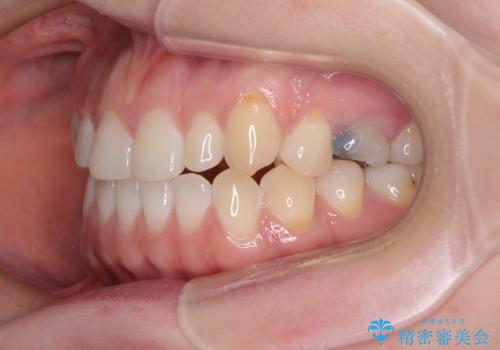

隙間の空いた歯列とボロボロの乳歯 インプラント治療と矯正治療

- 隙間の多い歯列や傾斜した奥歯、むし歯の酷い残存乳歯を気にして来院された患者様です。

傾斜した下顎の奥歯は、矯正治療にてまずは歯軸を改善させ、隙間が閉じられるようであればそのままに、閉じられないようであればインプラント治療を行うこととしました。

上顎のむし歯の酷い残存乳歯は抜歯をし、矯正治療の途中でインプラントを埋入、矯正治療後に補綴治療を行うこととしました。